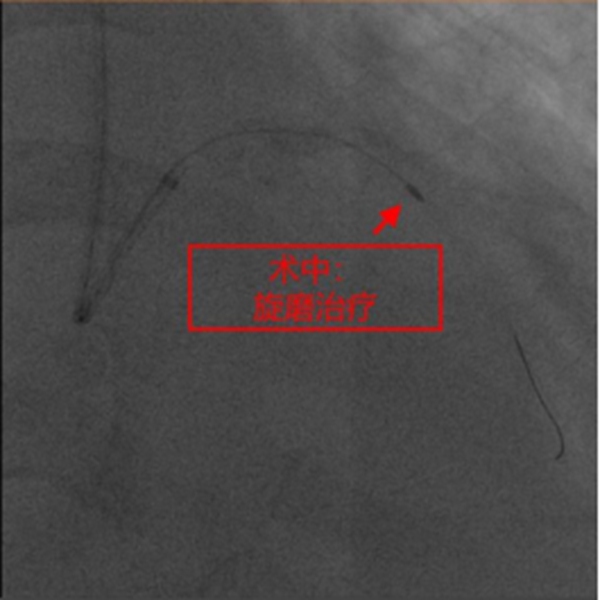

在征得患者及家屬同意,做好充分術(shù)前準備的情況下,冠脈介入團隊在冉擘力主任帶領(lǐng)下,按計劃給患者實施了血管內(nèi)超聲(IVUS)指導下經(jīng)皮冠脈旋磨+Shockwave沖擊波球囊碎裂鈣化斑塊及支架植入術(shù),術(shù)中團隊克服了一系列困難,最終安全順利地完成了全部介入手術(shù)過程,完全碎裂了環(huán)狀鈣化斑塊,效果非常滿意,歷時約1個多小時,手術(shù)成功,病人安返病房。術(shù)后患者胸悶、氣短明顯緩解,對治療效果十分滿意。